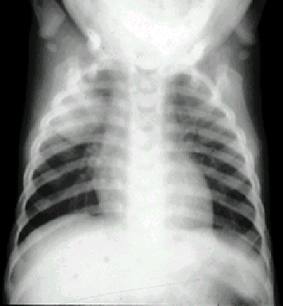

- RX tórax PA

y Lateral.*